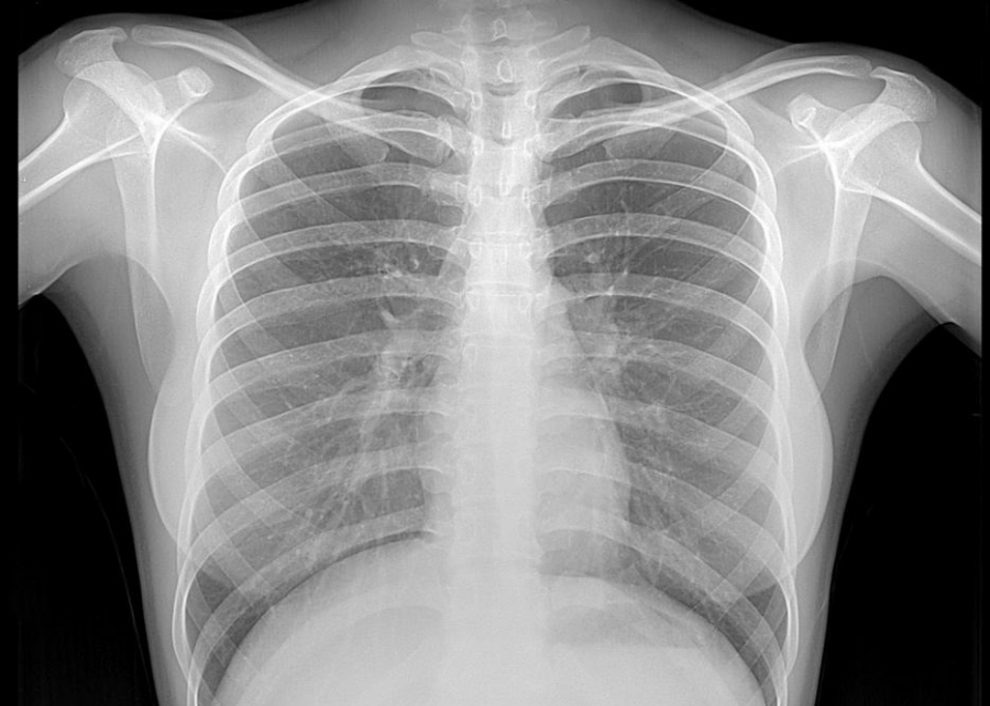

În general, o radiografie pulmonară efectuată cu un aparat bun nu depăşeşte 0,6 mSv, echivalentul a 15 zile de iradiere naturală (din apă, aer, mâncare, sol sau organisme vii), o radiografie abdominală echivalează cu şase luni de iradiere naturală (5 mSv), o tomografie computerizată, cu 1-2 ani de iradiere naturală (poate ajunge la 15 mSv), iar o radioscopie este echivalentul a 50-150 de radiografii (poate ajunge la 30 mSV).

Medicul radiolog trebuie să monitorizeze atent doza de radiaţii. “Toate aparatele au, conform legii, dispozitive de măsurare a dozei de radiaţii. Medicul trebuie să întocmească un buletin de radiaţii pentru fiecare şi atunci când pacientul se prezintă pentru o nouă radiografie, să-i poată spune dacă a acumulat sau nu o cantitate prea mare de radiaţii. Dacă da, atunci îl putem îndrepta spre investigaţii cu zero radiaţii, ecografie sau rezonanţă magnetică”, ne-a explicat prof. dr. Gheorghe Iana.